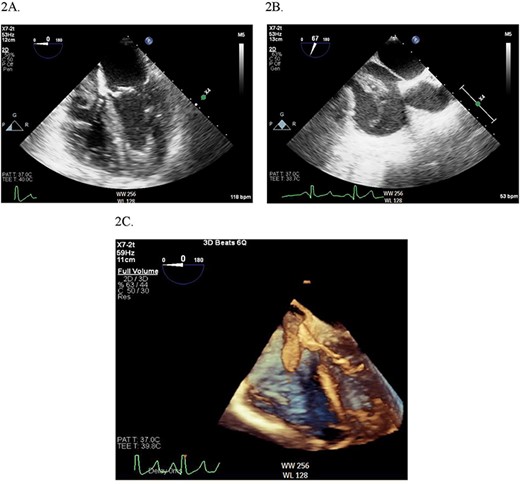

Continuous intraoperative transesophageal echocardiography (TEE) was performed. Postinduction TEE showed a large mobile mass of heterogeneous echogenicity in the RA abutting the tricuspid valve, mild tricuspid insufficiency, occlusive thrombus in the IVC and LV ejection fraction of 40% (Figs 2 and 3; Supplementary Materials S1 and S2). Given the location, size and mobility of the mass in the RA, the decision was made to remove it on CPB to minimize the risk of large embolus and significant blood loss. During the prebypass period, following laparotomy and drainage of abdominal ascites, the patient required significant colloid repletion with 5% albumin and blood products for hypotension, underfilled LV on TEE and low central venous pressure.

(A) Midesophageal four chamber TEE view showing large mobile mass of heterogeneous echogenicity in the RA. (B) Another view of the RA mass in a midesophageal bicaval view. (C) 3D illustration of the RA mass.